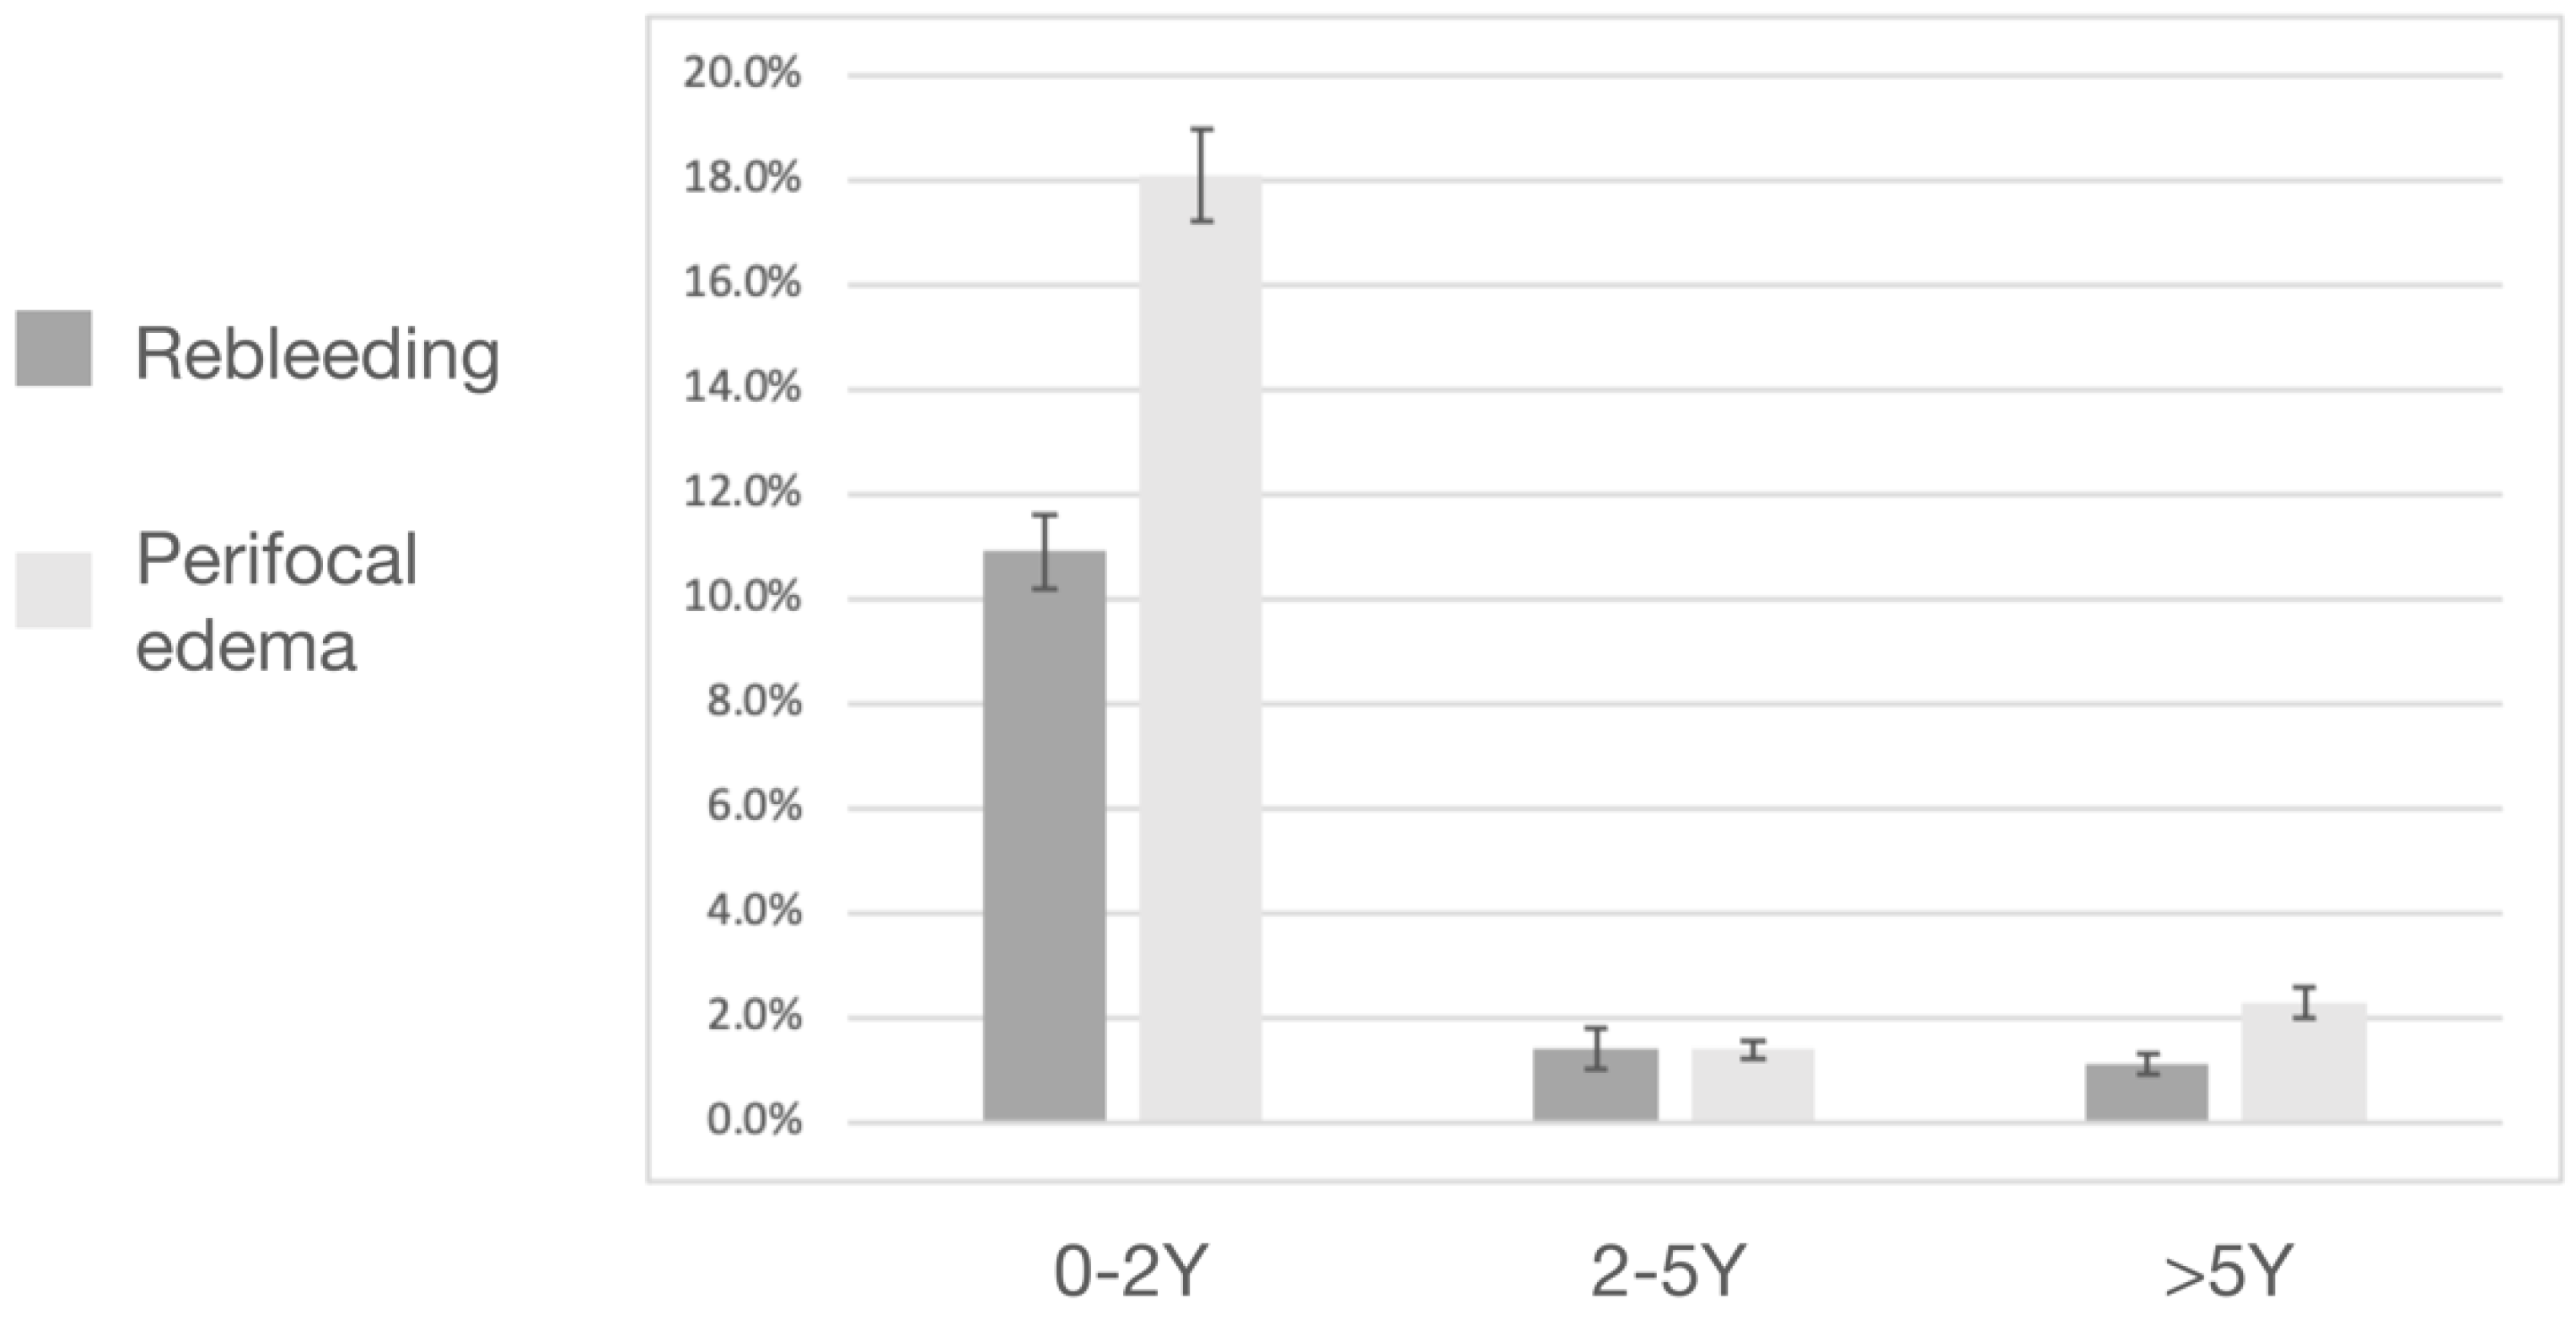

3.2. Post-Radiosurgical Rebleeding Analysis

3.4. Post-Radiosurgical Perifocal Brain Edema